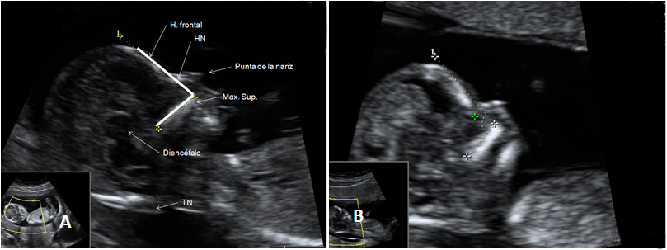

Ecografía Embarazo 2D y 3D Semana 12 - PRUEBAS DIAGNÓSTICAS

Ecografía Embarazo 4D Semana 12 - PRUEBAS DIAGNÓSTICAS